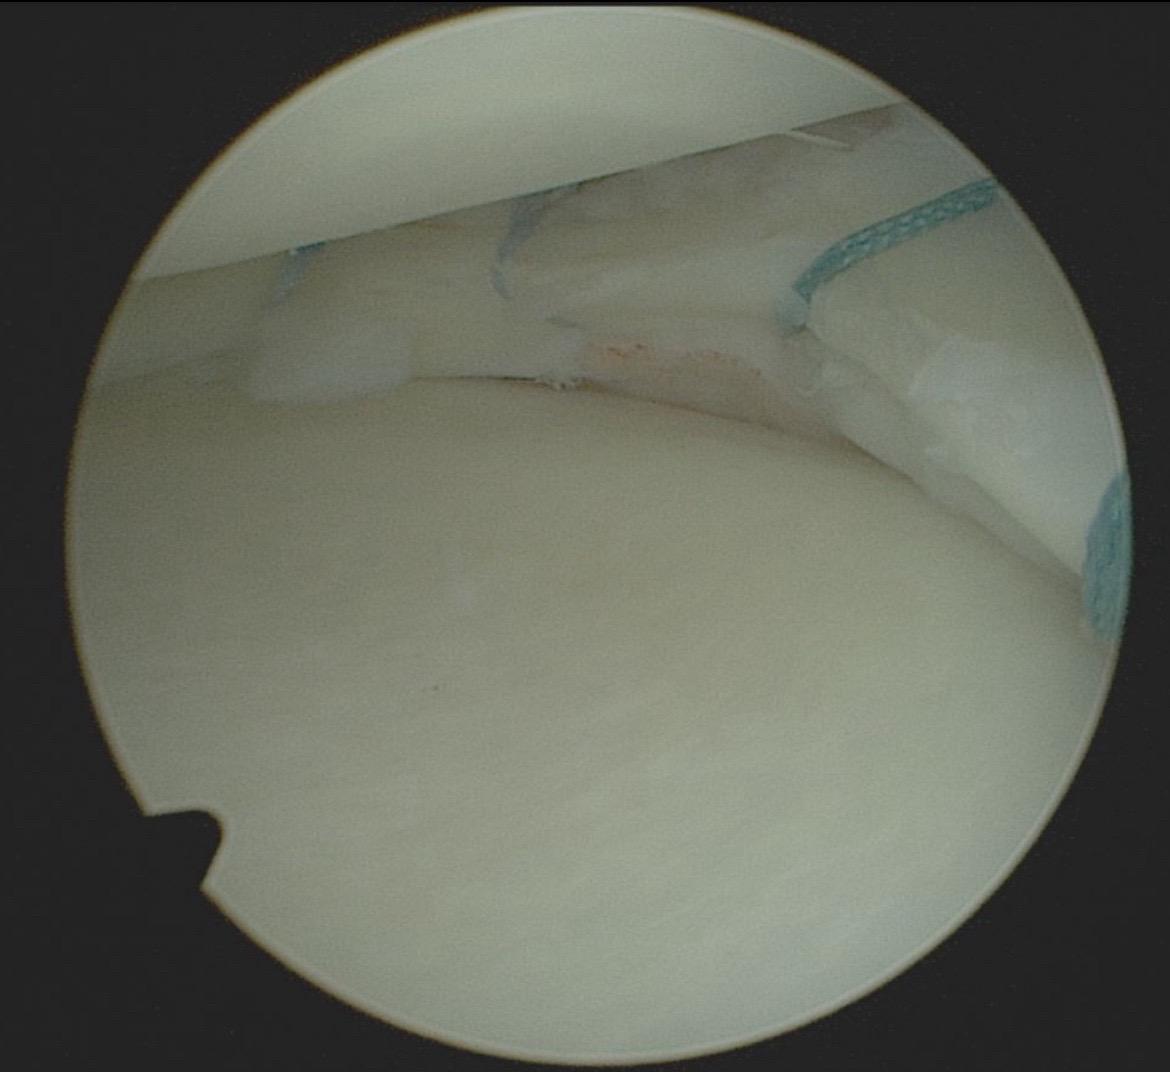

前交叉韧带重建。前叉重建+半月板修复,祝他早日康复!

半月板修复,不是小打小闹!手术关键,微创技术显神通

半月板修复,不是小打小闹!手术关键时刻,缝合技术超精细,恢复快才是王道

半月板修复,不是小打小闹!手术关键,关节镜下精细化操作,术后康复才是漫长跑道

半月板修复,不是小打小闹!手术关键,恢复计划超讲究。从撕裂到重返赛场,每一步都是挑战,加油康复,王者必归!🔥💥